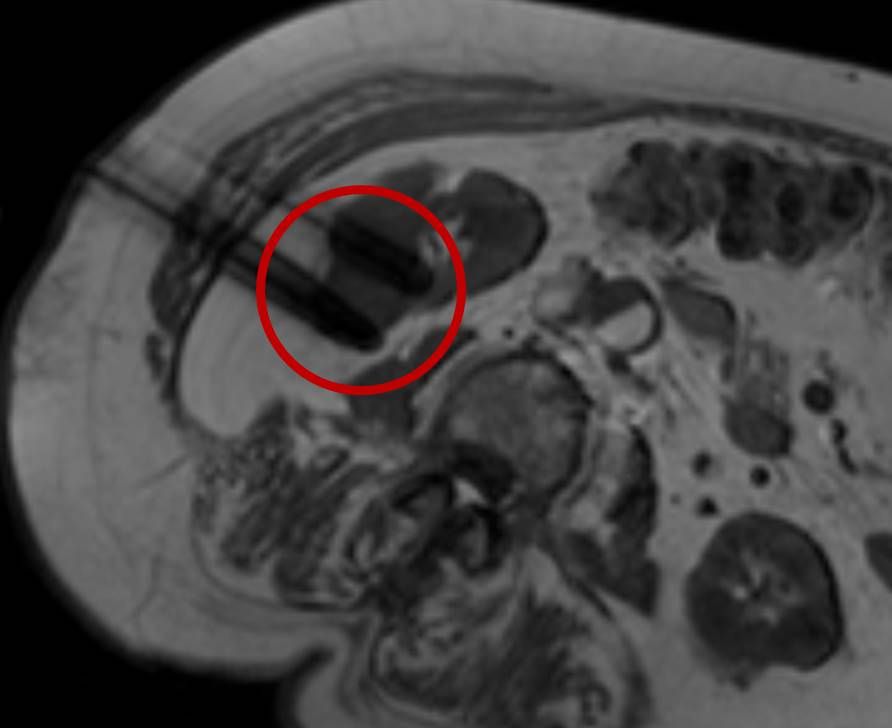

Abbildung: Osteoidosteom (Pfeil) im Schienbein bei einem jungen Patienten. Unter CT-Bildgebung wird ein spezieller Applikatoren unter CT-Bildgebung in das Osteoidosteom eingebracht. Durch Hitze wird dieses effektiv und dauerhaft zerstört.